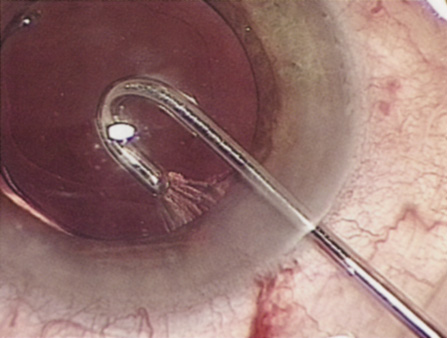

HYDRODISSECTION

Hydrodissection can be performed after the surgeon has successfully completed capsulorrhexis.97 If the capsulorrhexis is not intact, fluid forced around the interior of the capsule may cause the bag to splay open. With capsulorrhexis, hydrodissection is a safe and extremely useful maneuver. Hydrodissection can be thought of as two maneuvers: hydrodelineation and cortical cleaving hydrodissection. By placing a 27-gauge cannula on a syringe filled with balanced saline solution (BSS), the surgeon can direct fluid beneath the residual anterior capsular rim to create a cleavage plane. Depending on the direction the fluid wave takes, different lamellae of the cataract will be separated. Hydrodelineation is the term used when the cleavage plane separates the adult nucleus from the fetal nucleus or the adult nucleus from the more peripheral epinucleus. Hydrodelineation often results in the characteristic golden ring sign (Fig. 11). Cortical cleavage occurs when the cortex is separated from the capsular bag (Fig. 12). Finding the cortical cleavage plane may be facilitated by gently lifting the capsular margin away from the cortex with the BSS cannula before injecting. Several small bursts of fluid allow the surgeon to monitor progress of the fluid wave. When dealing with a soft nucleus, the authors strive to perform true cortical cleaving hydrodissection. For a hard nucleus, hydrodelineation allows manipulation of less of the nuclear bulk, although the remaining epinuclear shell must be addressed in an additional step. Hydrodelineation is particularly useful if the nucleus is not freely mobile after cortical cleaving hydrodissection.

Fig. 11. A crisp “golden ring” is seen from the fluid cleft between the epinucleus and nucleus with hydrodelineation.

Fig. 12. Hydrodissection, performed subincisionally with a 27-gauge J-cannula, produces a cleavage plane between the capsule and the cortex. The small blue arrows indicate the advancing fluid wave.